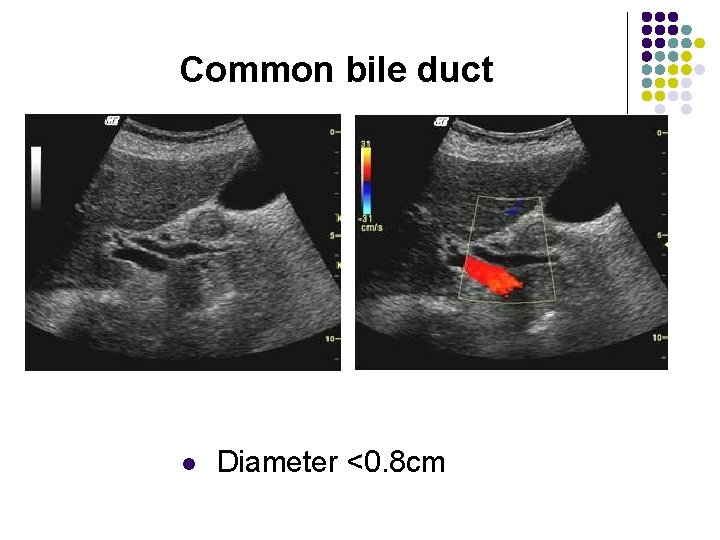

Common bile duct l Diameter <0. 8 cm